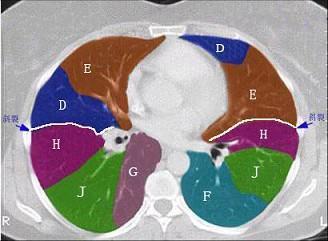

问题 结合肺段模式肺动脉干与右肺动脉层面、心室层面、主动脉弓层面、左右心房层面图(如图),选出左肺下叶的组成 ( )

选项 A.G+H+I+J B.F +H+I+J C.E+F+G+H+I+J D.D+E+F+G+H+I+J E.C+D+E+F+G+H+I+J

答案 B